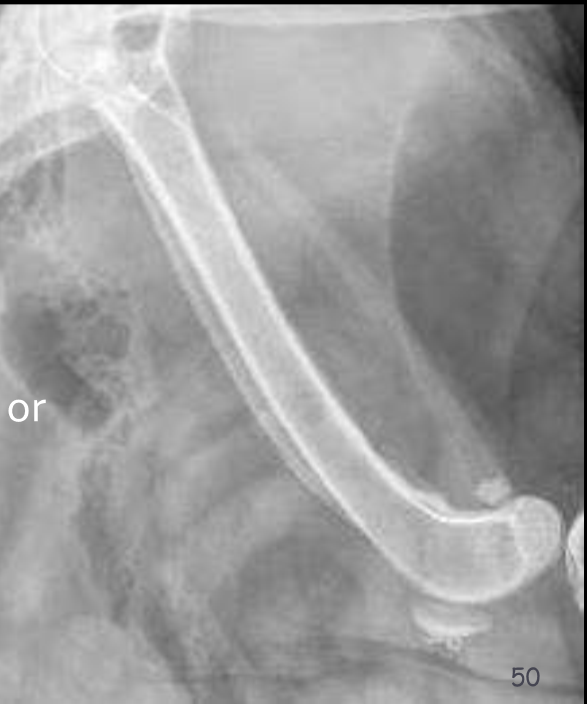

Hypertrophic osteopathy

Diseases like hypertrophic osteopathy